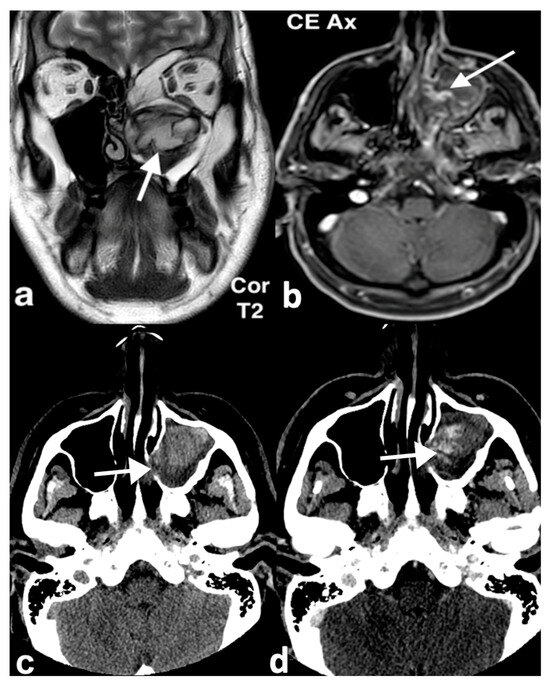

3.1.2. Rinolith